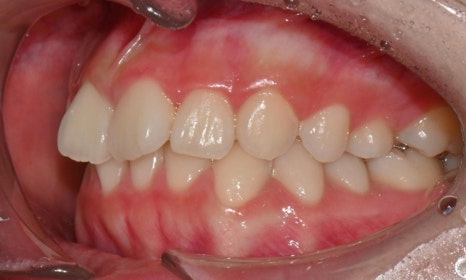

치료 과정 중 환자는 장치 착용 시간을 매우 잘 지켜주었고, 내원 시마다 계획한 치아 이동이 비교적 정확하게 이루어지는 모습을 보였습니다. 이처럼 인비절라인 치료의 경우 환자의 협조도가 치료 결과에 큰 영향을 미치기 때문에, 이번 케이스에서는 환자의 성실한 장치 착용이 좋은 결과를 만드는 데 중요한 역할을 했다고 볼 수 있습니다.

치료 시작 8개월 후 마무리 - 연세정원치과

치료 후 전치부 배열이 정리되면서 웃을 때 스마일 라인도 한층 자연스럽게 개선되었습니다. 과개교합 역시 기능적으로 안정된 상태로 마무리할 수 있었습니다. 치료 후반부에 아주 경미한 중심선 차이가 남아 추가 장치를 통한 마무리를 권유드렸으나, 환자가 고2 학생으로 학업 일정이 바쁜 시기였고 현재 결과에 대해 본인과 보호자 모두 충분히 만족하여 이 상태에서 치료를 종료하기로 하였습니다.

무엇보다 이 환자는 8개월 동안의 치료 전반에 걸쳐 장치 착용을 매우 잘 지켜준 성실한 학생이었고, 그 결과 비교적 33단계의 효율적인 장치 갯수만으로도 안정적이고 만족스러운 결과를 얻을 수 있었습니다.